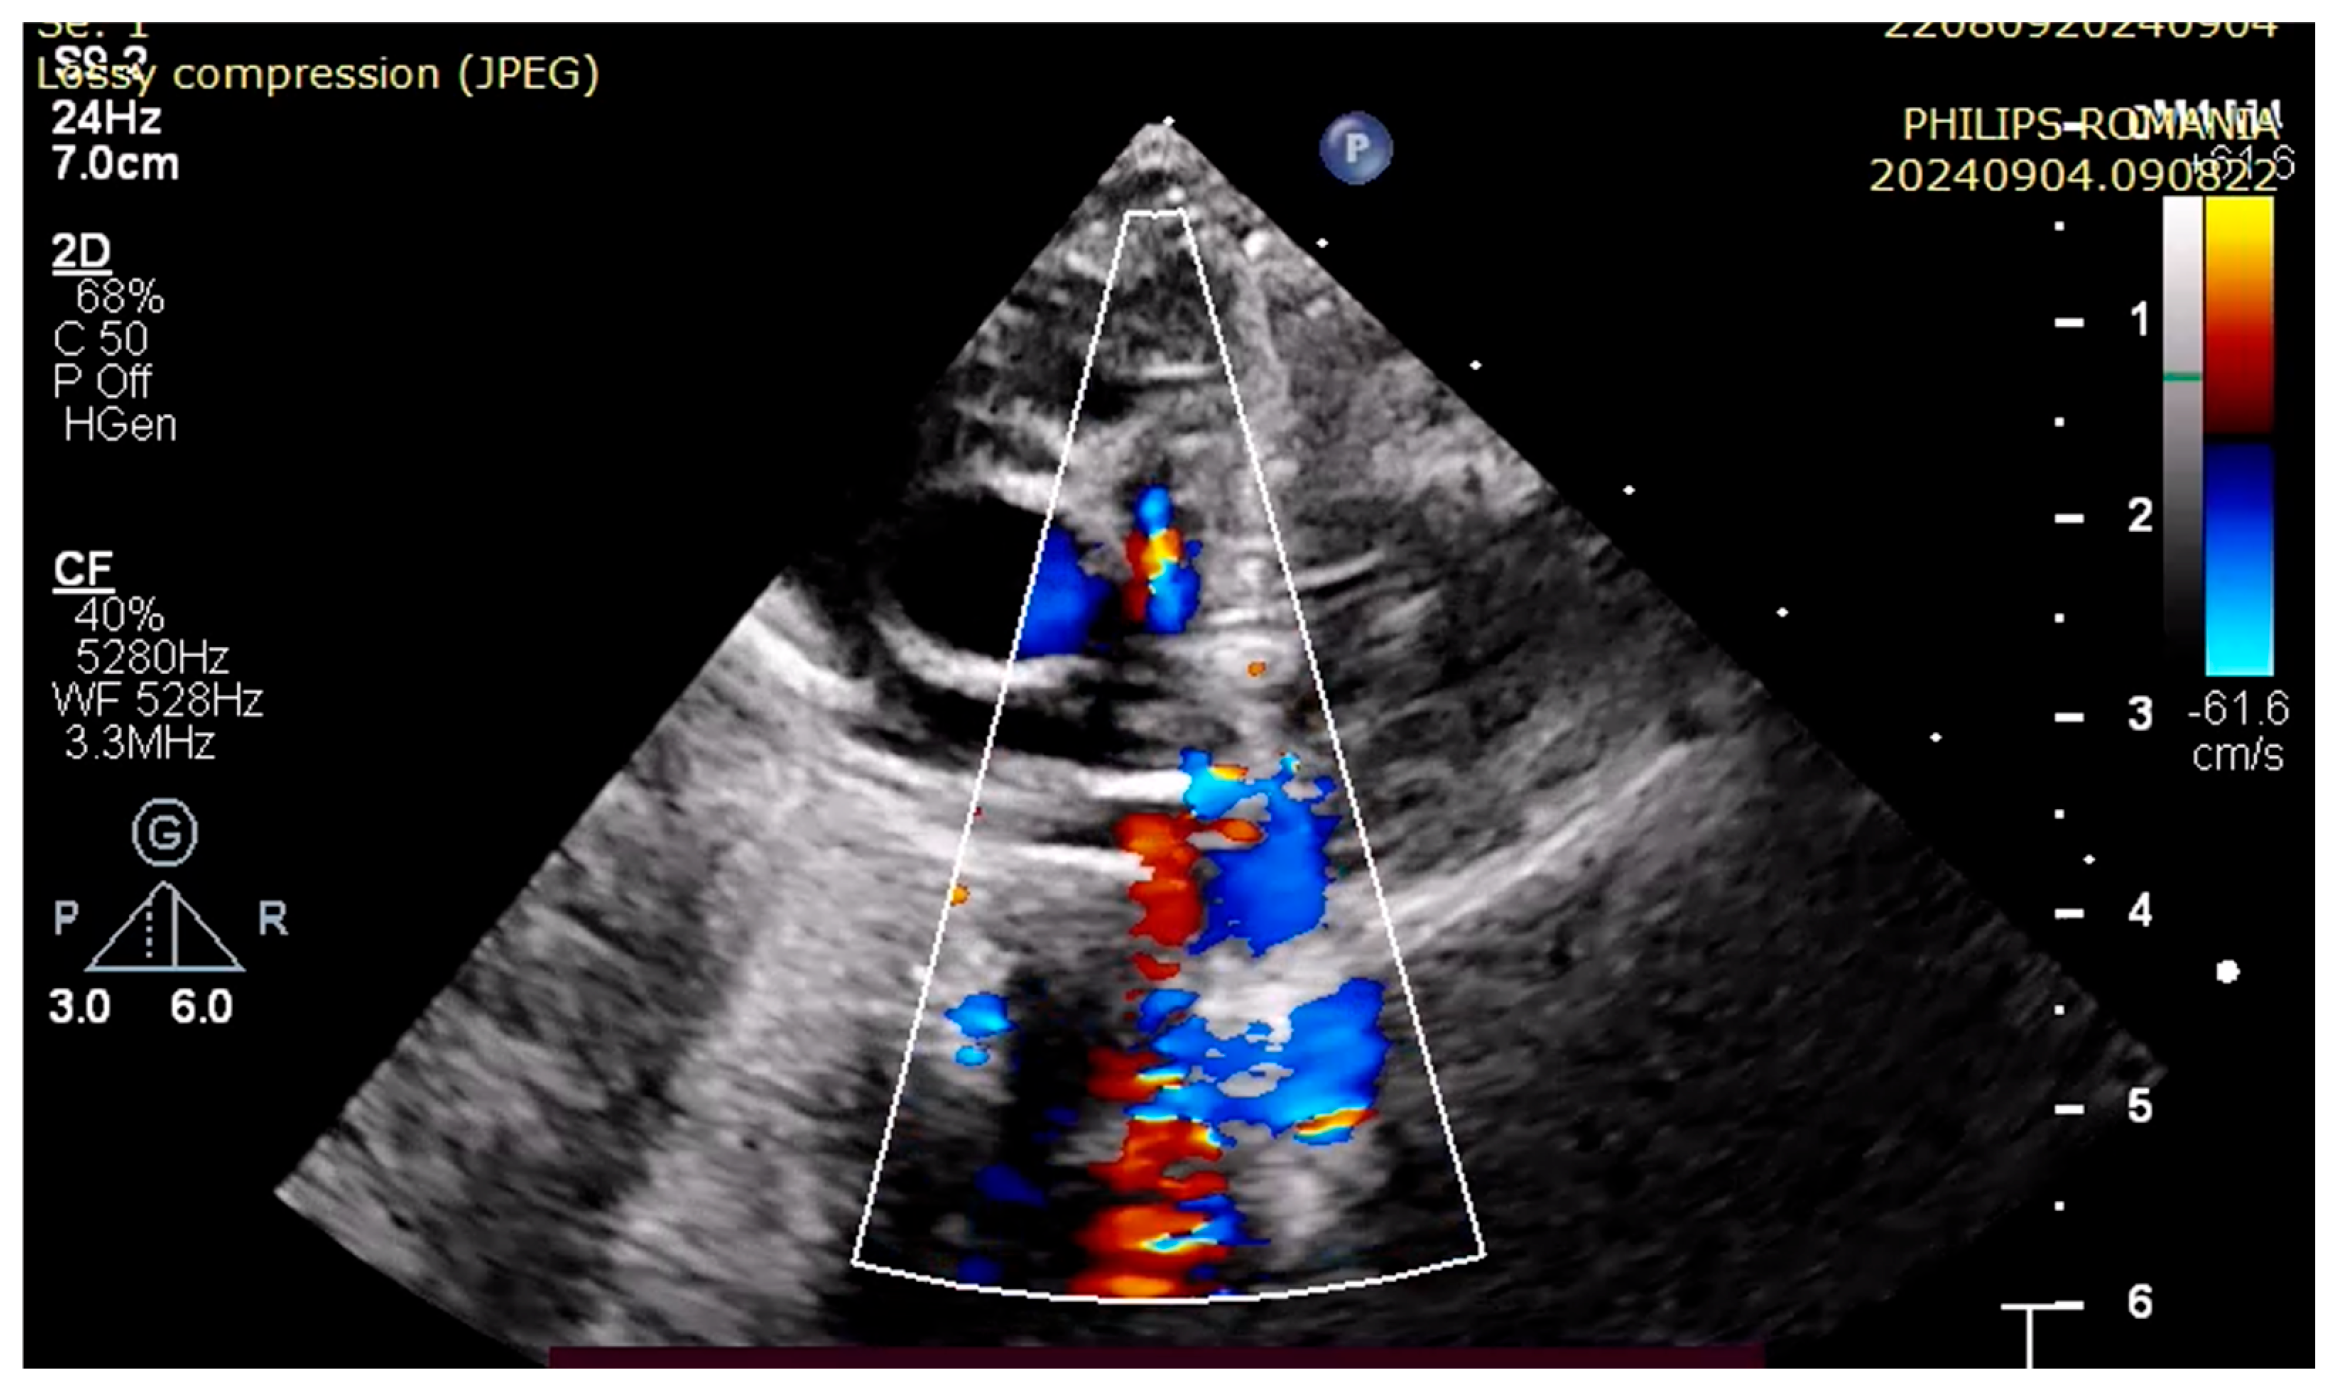

4. Case Reports